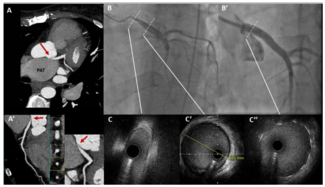

A 52-year-old diabetic, hypertensive male presented with progressive dyspnea and palpitation for the last 3 months. Clinical examination revealed low blood pressure in lower limbs with an ankle-brachial index (ABI) of 0.50. Systemic...